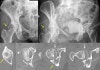

대퇴골두 골절의 분류(Pipkin classification)

Type 1 : Fracture inferior to fovea

Type 2 : Fracture superior to fovea

Type 3 : Fracture of femoral head with fracture of femoral neck

Type 4 : Fracture of femoral head with acetabulum fracture